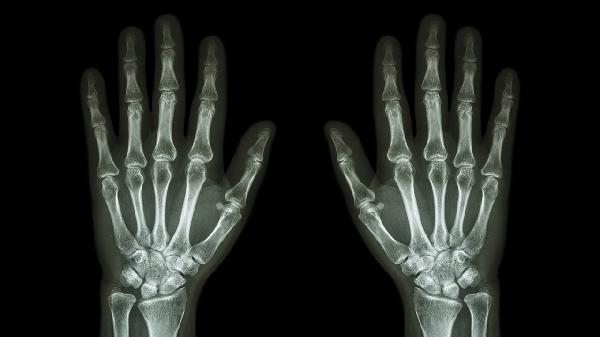

三角骨骨折通常由外伤、运动损伤、骨质疏松等因素引起,可通过保守治疗、药物治疗、手术治疗等方式干预。三角骨骨折可能与直接暴力、间接暴力、骨骼疾病等因素有关,通常表现为局部疼痛、肿胀、活动受限等症状。

三角骨骨折康复期应避免患肢负重,定期复查X线观察愈合情况。饮食注意补充富含钙质的乳制品、深绿色蔬菜,配合适度的手部抓握训练维持肌力。恢复运动需循序渐进,使用护腕提供支撑保护。若出现持续疼痛或活动障碍,应及时复诊排除延迟愈合或不愈合可能。